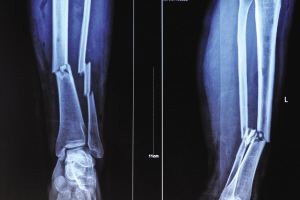

举两个例子说明一下医生怎么通过“黑白色差”判断病情:

一、比方说某患者小腿出现明显骨折,那他骨折处对X光的吸收量就与周边骨干呈现出明显对比,骨折处就会出现一条明显的黑色裂痕。再者,医生也会通过白色“画成”的骨干是否有异常变形做判断。

二、部分患者并非因为骨折去拍片,而是因为骨头里进了异物。要想通过手术取出来,首先得准确判断异物在骨干精确到毫米的位置。医生怎么判断呢?异物在骨头内对X光的吸收量不同,那个点就会与周边骨干呈现出明显色差,一般是白色的骨干当中出现明显的黑点。通过这一异常医生就可以锁定异物位置。

X光一般是初筛,对体内异物的直观诊断。对于有移位骨折、有骨质改变的骨病、关节部位骨性病变、不透光异物存留、心肺器质性疾病、消化系统梗阻等疾病有很好的诊断价值。X光的优点是对于骨干病变的诊断,但对于体内的软组织检查没有太多效果。